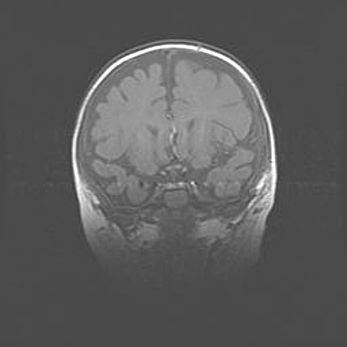

Открытая гидроцефалия.

Возраст: 6 месяцев 15 дней

Вес: 6200 г

Пол: женский

Окружность головы: 41 см

Срок гестации: 38 недель

Гидроцефалия головного мозга у новорожденных – это скопление избыточного количества цереброспинальной жидкости в головном мозге. Ее избыточное скопление в мозге приводит к патологическому расширению желудочков мозга (четырех полостей, расположенных в глубине белого вещества мозга, заполненных цереброспинальной жидкостью и связанных узкими проходами).

Открытый тип гидроцефалии (сообщающаяся) наблюдается тогда, когда нарушен механизм всасывания ликвора в системный кровоток. При этом типе причиной заболевания чаще всего является перенесенные ранее инфекции (например: менингит),  либо же наличие крови в субарахноидальном пространстве.